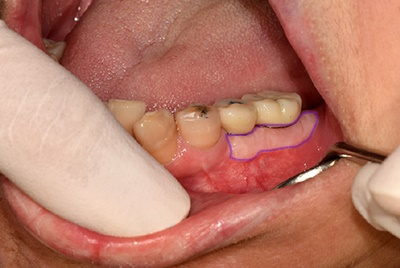

아래 사진을 보실까요?

치아가 없으신 상태로 오랜 시간 방치를 한 45세 여성 환자분의 사진입니다.

대부분의 환자분들은 치조골 이식 후 임플란트를 식립하는 경우가 대부분이지만 아래 환자분은

잇몸까지 너무 얇아서 푹 꺼져있습니다.

아래 환자분의 경우 뼈이식을 하고 임플란트를 식립 하셔도

예후가 좋지 않을 것이 너무도 뻔합니다.

따라서 이러한 케이스의 경우 잇몸이식(치은이식술)을 고려하게 됩니다.

첫번째 치료전 사진의 푹 꺼져 있는 잇몸이 치료 후에는 두번째 사진처럼 두꺼운 잇몸이되어 임플란트를

안정적으로 오래 유지하는데 많은 도움을 주게됩니다.

물론 이식한 조직의 색깔도 시간이 지남에따라 자연스럽게 바뀝니다.